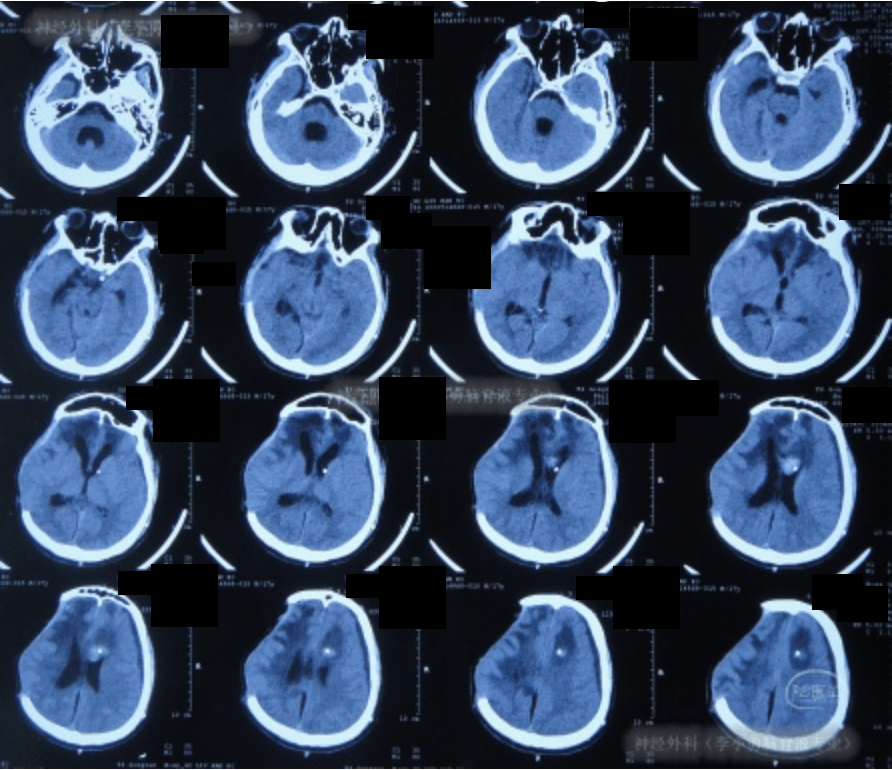

入院时头颅ct示双侧额顶枕叶及颞叶脑损伤,脑室系统扩张,内见点片状

图-6:2024年10月19日头颅ct入院时头颅ct示双侧额顶枕叶及颞叶脑损伤

图-6:2021年1月17日头颅ct脑室外引流5天即2021年1月17日,查头颅ct时